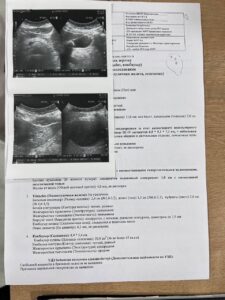

Кульжанова Ардак Туленовна 31 декабря 1960 года рождения, в марте 2024 с кровотечением поступила в ТОО » Национальный научный онкологический центр», где был выставлен диагноз » эхинококкоз печени».

На УЗИ от 06.11.2024 наблюдается положительная динамика.